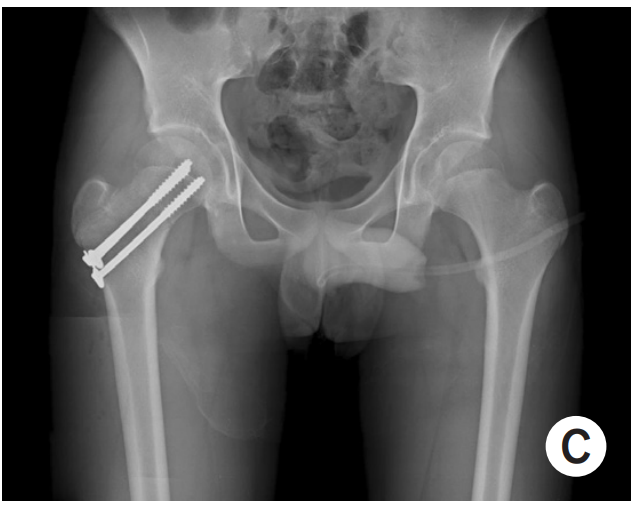

기본적으로 시행하는 x-ray 및 피검사 외에도 MRI 검사를 통해서 고관절 내 농양 형성 여부 및 골수내 침범을 확인하게 됩니다.

그리고 입원하여, 응급 수술을 하게 됩니다.

앞에서 말씀드린 것처럼 고관절을 녹이는 경과를 보이기에 몇 시간이라도 빠르게 수술해야하는 응급 수술입니다.

(수술은 주로 절개 배농술을 시행하게 되는데, 고관절 내의 농양을 빼주고 세척해주는 수술을 하게 됩니다)

응급 수술 결과, 예상대로 고관절에 농양이 형성되고 있었다면, 항생제 치료를 입원기간동안 지속하게 됩니다

다행히도, 농양 형성이 없다면, 몇일 간의 관찰 기간을 거쳐서 퇴원하게 됩니다.